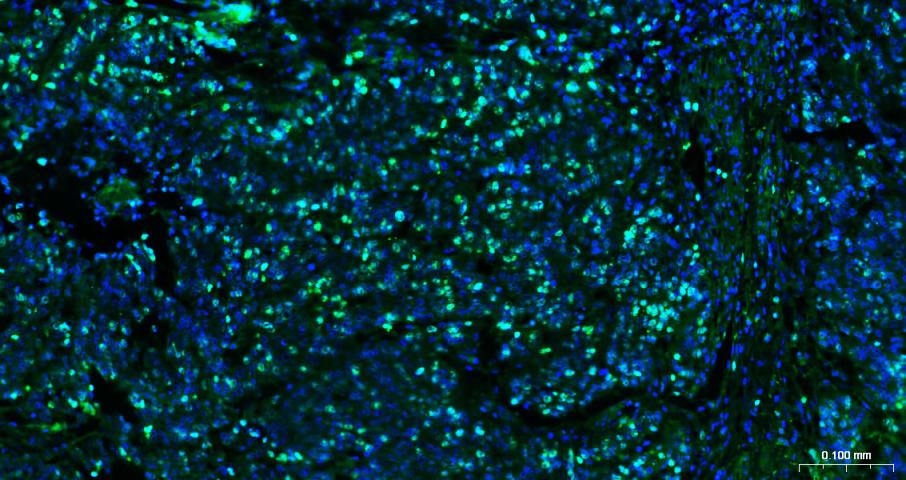

IFHuman, Mouse, Rat1:100-500

ICC/IFHumanMouse, Rat1:100-500